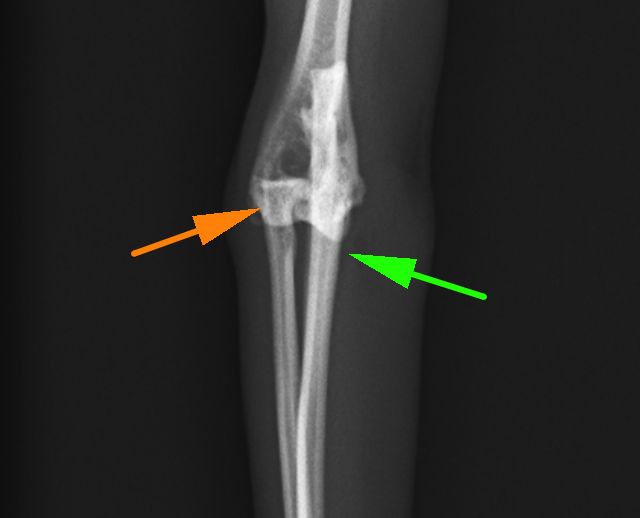

患肢を正面から見たX線画像です。オレンジの橈骨と緑の尺骨が離れており、脱臼しているのが分かります。